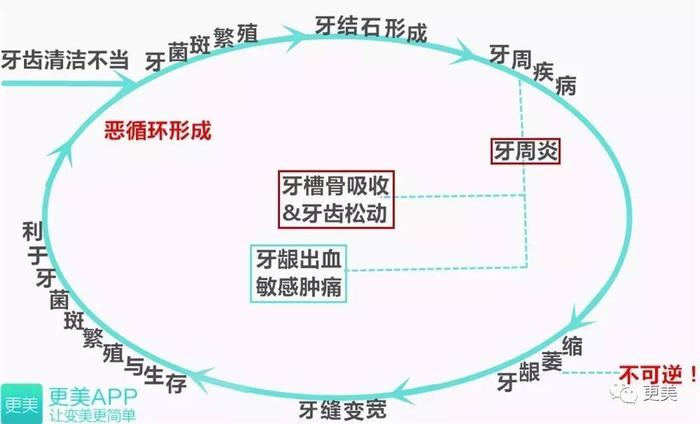

另外,牙菌斑对牙龈和牙根也都有破坏作用,引起牙龈炎,进一步可发展成牙周炎,破坏牙槽骨(让牙缝变宽的真正元凶在这儿啊!),让牙齿松动、脱落。

一张图就能搞懂↓